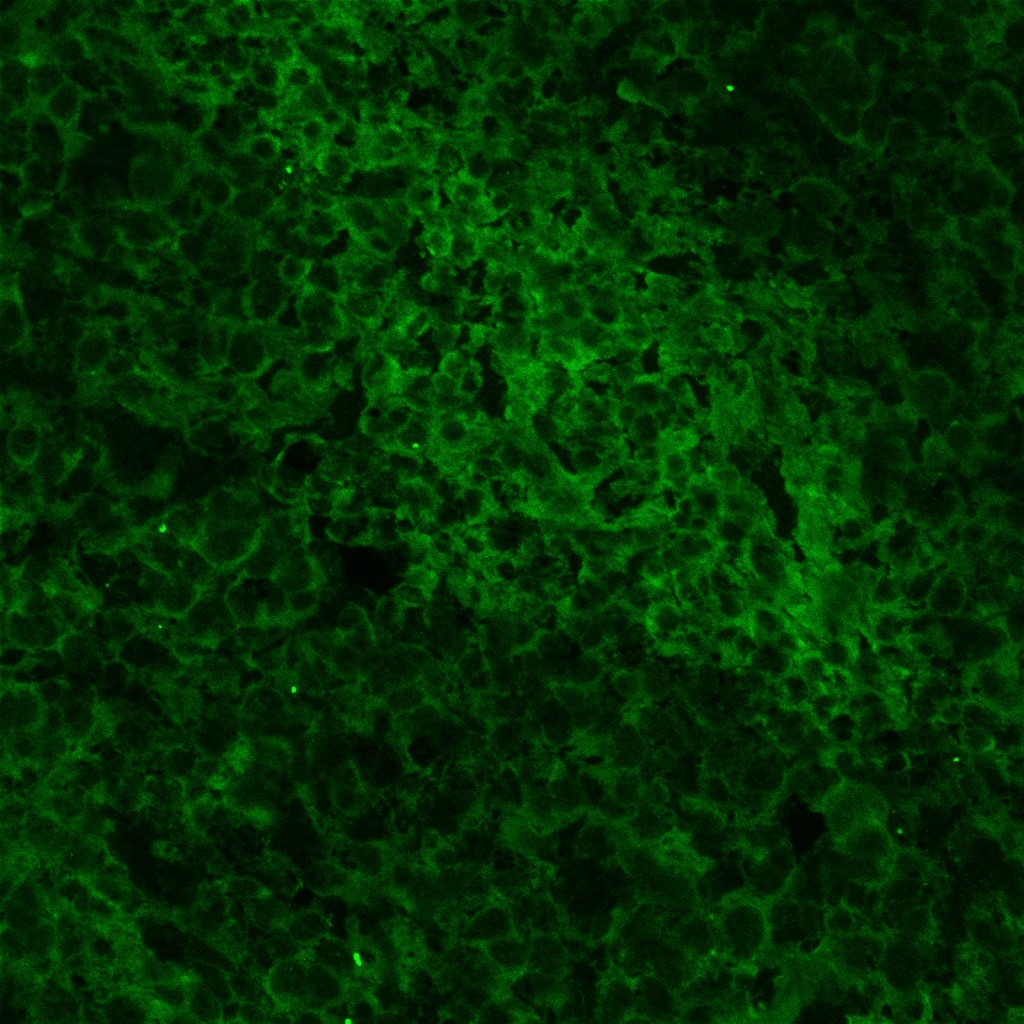

Detection of Human PD-L1 by Immunocytochemistry/ Immunofluorescence Human pancreas tissue from type 1 diabetic subjects express PD-L1. Human pancreas sections from type 1 diabetic (T1D), autoantibody positive (AA+), type 2 diabetic (T2D), and non-diabetic controls (NDB) were obtained from the Network for Pancreatic Organ Donation (nPOD) and stained for T cell markers (CD4, CD8), insulin, and PD-L1. Shown are representative islets from each group with 7–15 unique islets analyzed from three independent experiments with one patient per group. Scale bar corresponds to 20 µm. Image collected and cropped by CiteAb from the following open publication (https://pubmed.ncbi.nlm.nih.gov/29844327), licensed under a CC-BY license. Not internally tested by R&D Systems.